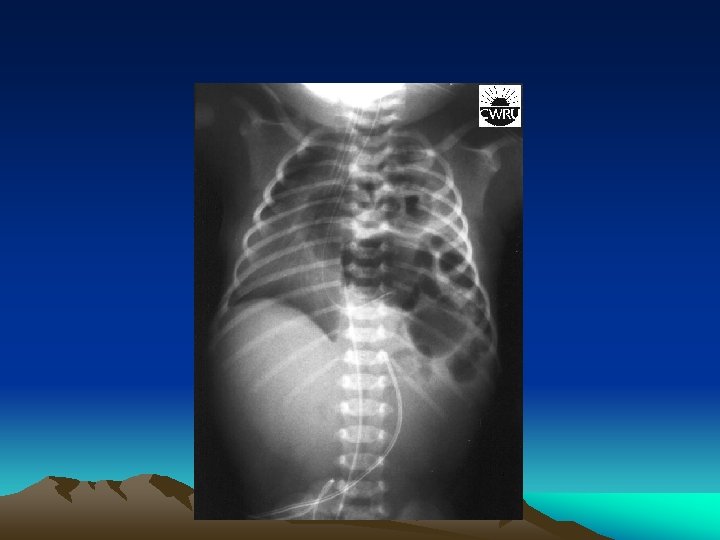

Bochdalek hernia • Called a postero-lateral diaphragmatic hernia. • The most common of CDH (95% ). • characterized by a hole in the postero-lateral corner of the diaphragm which allows passage of the abdominal viscera into the chest cavity. • The majority (80 -85%) occur on the left side of the diaphragm.

Presentation • Infants born with diaphragmatic hernia experience respiratory distress and failure due to both : pulmonary hypertension and pulmonary hypoplasia.

Diagnosis • This condition can often be diagnosed before birth (u/s). • X- ray chest • CT chest • Contrast study of the GIT